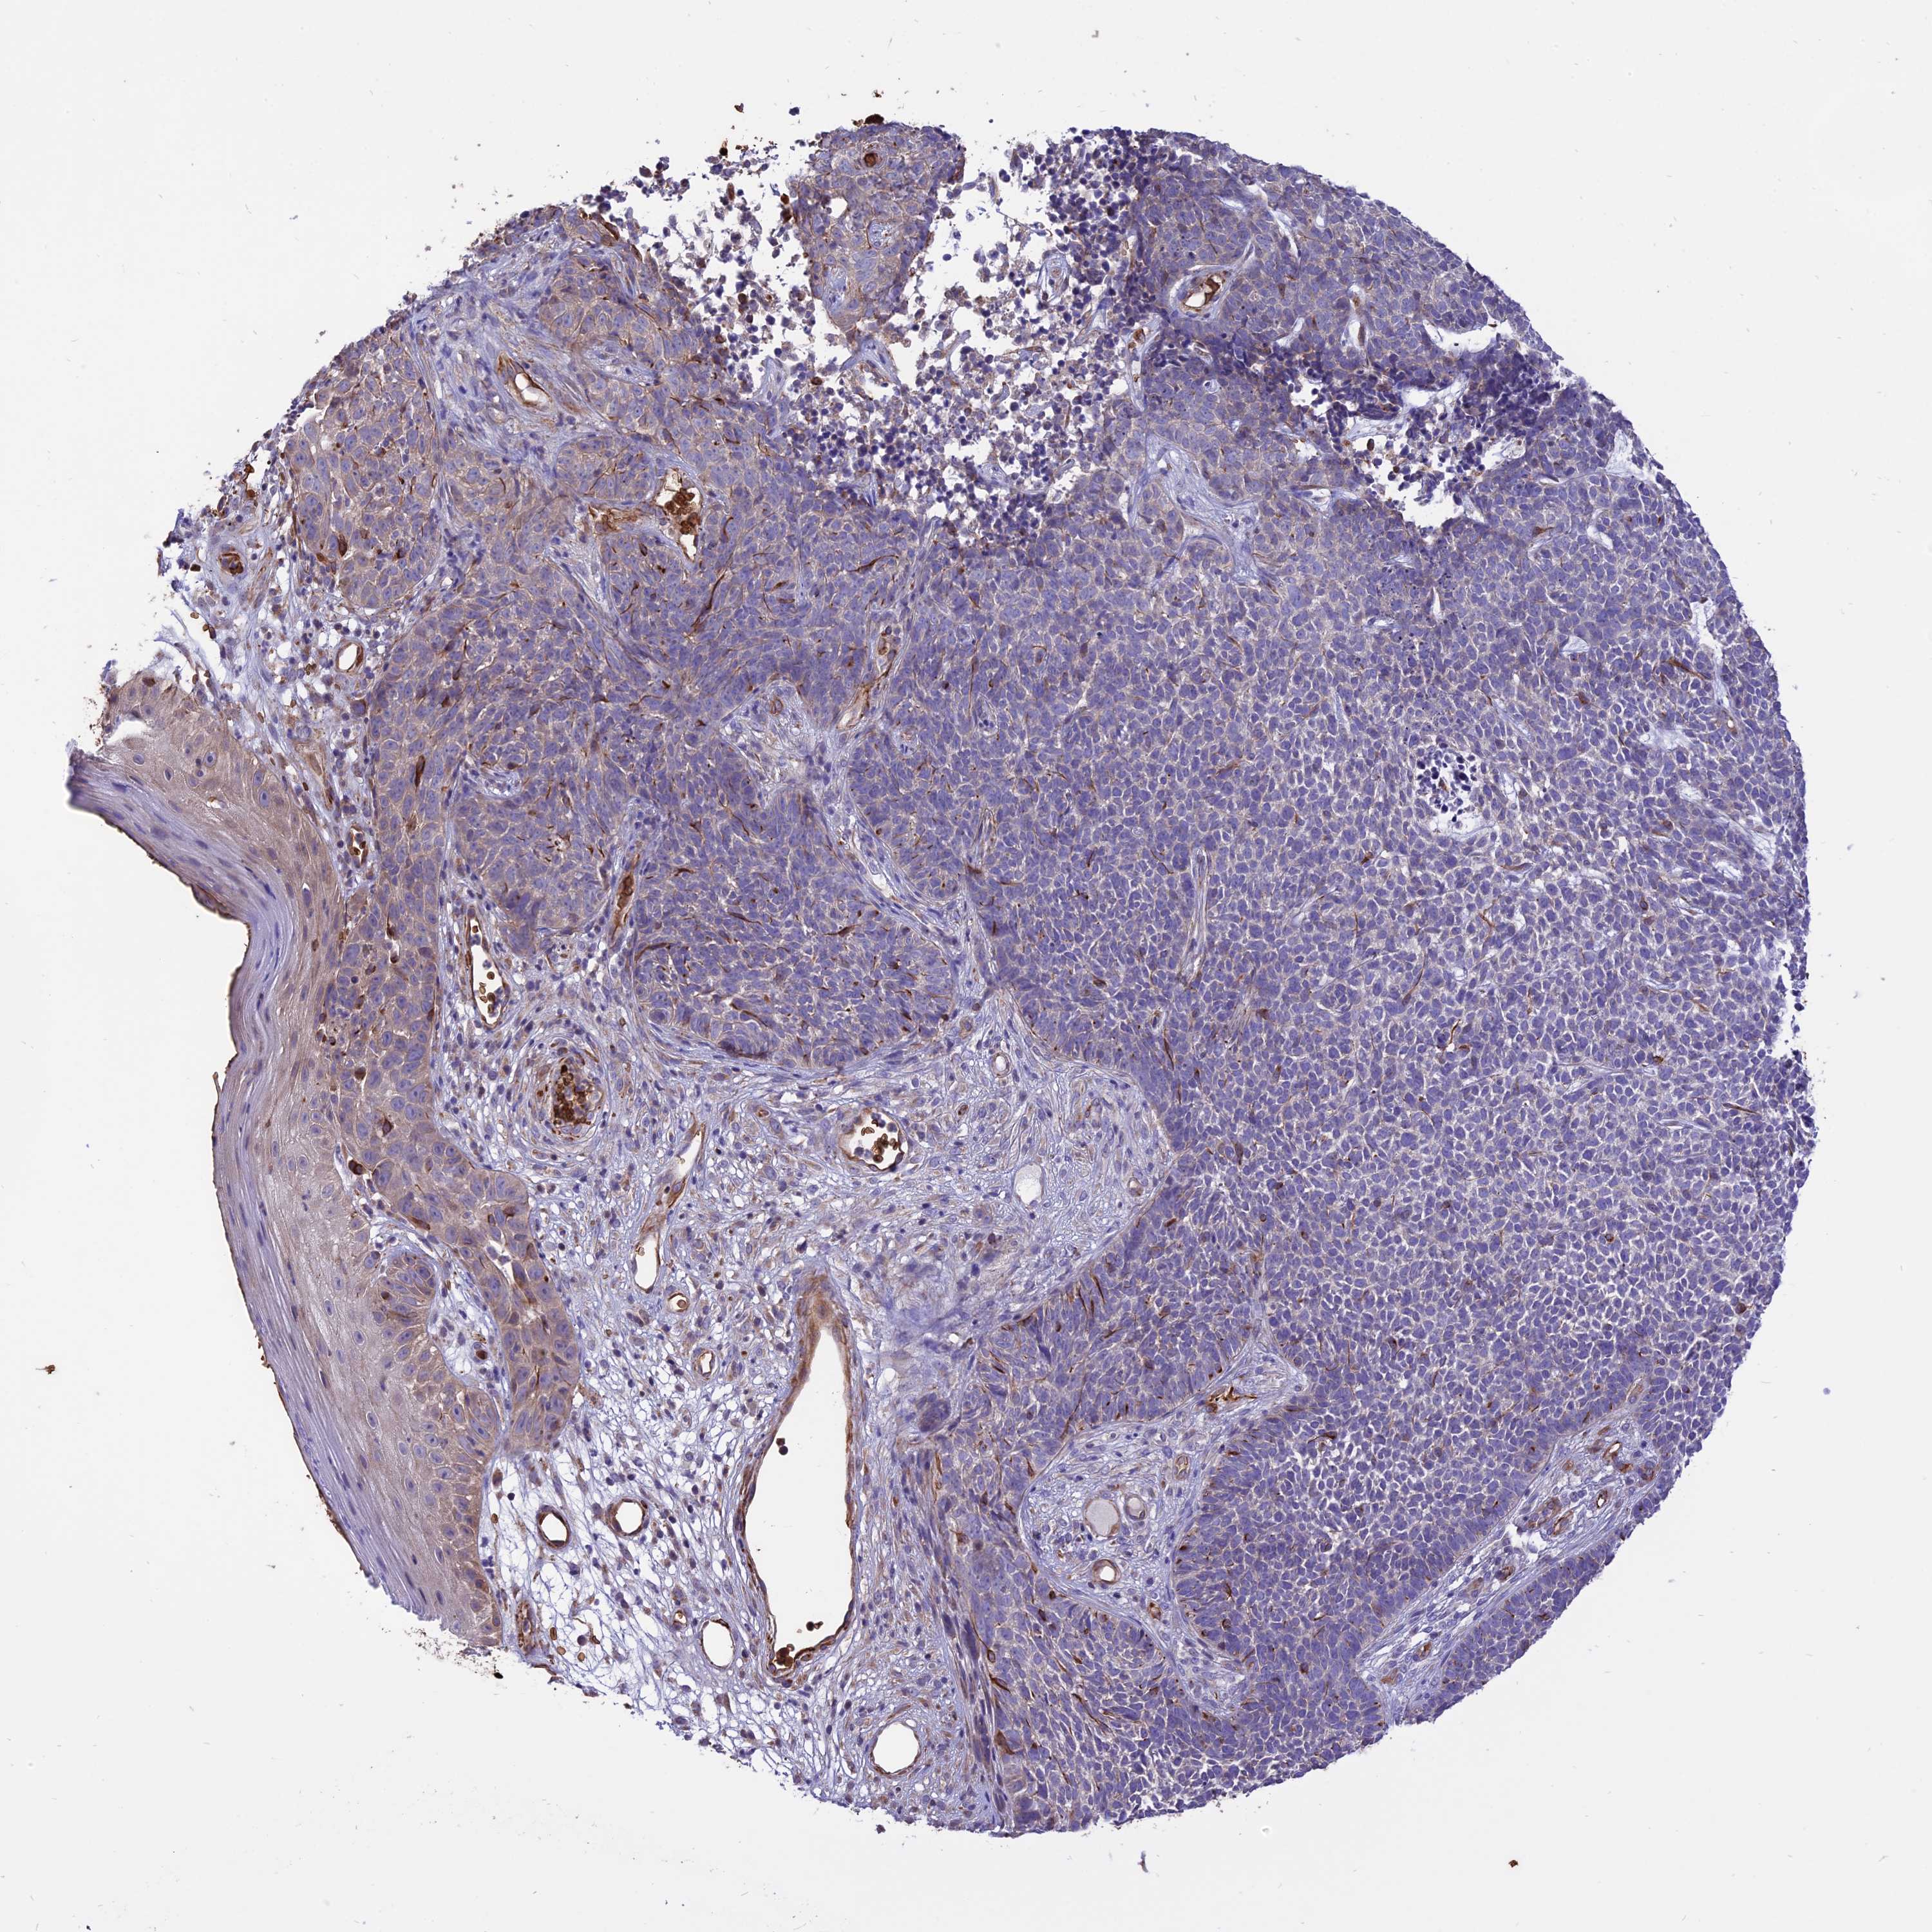

SKIN CANCER - Protein expressioni

A mouse-over function shows sample information and annotation data. Click on an image to view it in a full screen mode. Samples can be filtered based on level of antibody staining by selecting one or several of the following categories: high, medium, low and not detected. The assay and annotation is described here.

Each image is clickable and will lead to virtual microscopy that enables deeper exploration of all samples and also displays staining intensity scores, fraction scores and subcellular localization as well as patient and tissue information for each sample.

Antibody HPA042459

High

Intensity

Quantity

Location

Squamous cell carcinoma, NOS